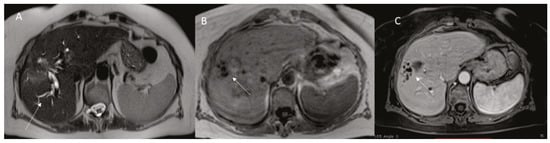

Abscess